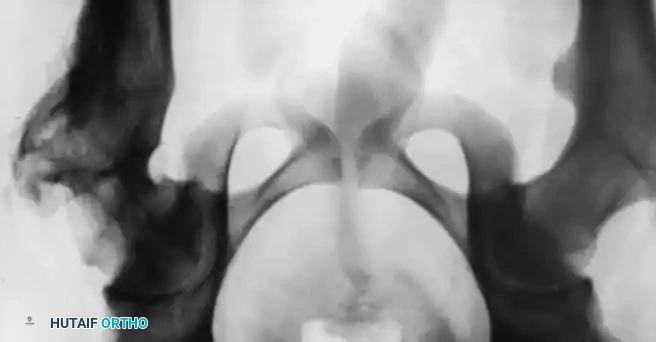

Standard evaluation mandates an anteroposterior (AP) radiograph of the pelvis and a cross-table (true) lateral view of the affected hip.

* Lateral Radiograph: Crucial for determining the extent of posterior displacement. The normal head-shaft angle on the lateral view is 170 degrees or more.

Radiographic Gallery: Diagnosis and Evaluation

Associated Surgical & Radiographic Imaging